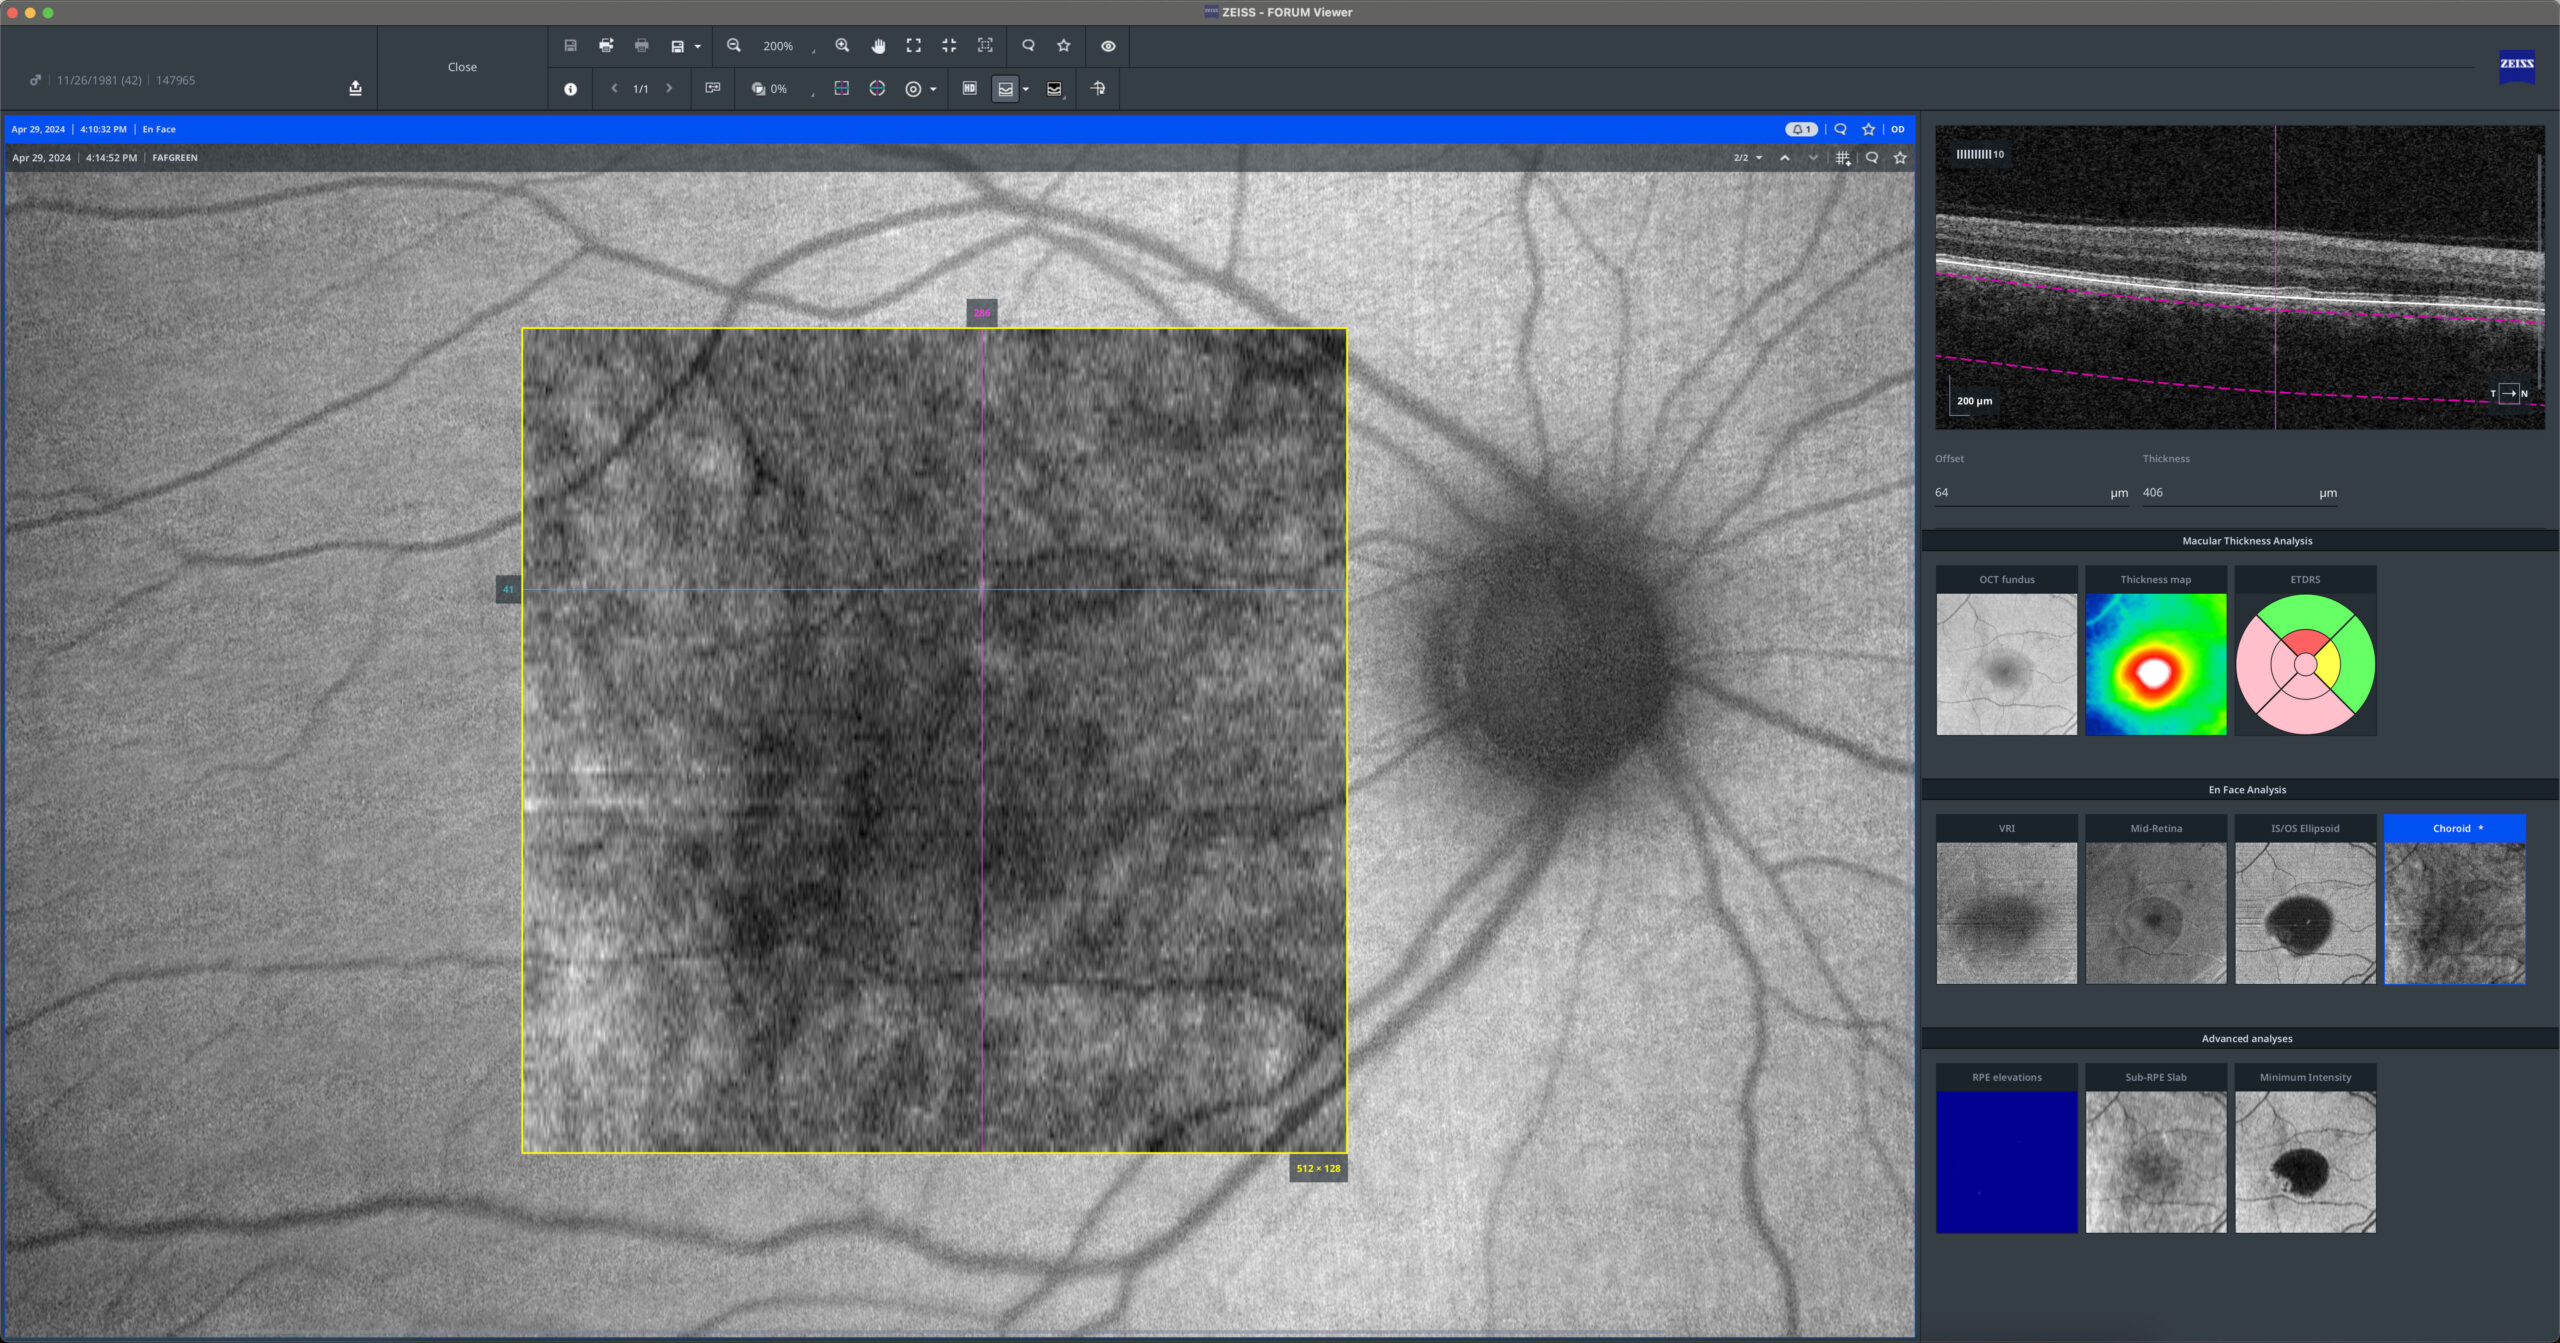

Central Serous Chorioretinopathy

40yo

40yo In Central Serous Chorioretinopathy (CSC), serous retinal detachment and serous pigment epithelial detachment (PED) are hallmark findings. Optical Coherence Tomography (OCT) reveals a hyporeflective space beneath the neurosensory retina and PEDs, often associated with focal RPE abnormalities. The leakage site at the RPE can be identified on OCT as a […]